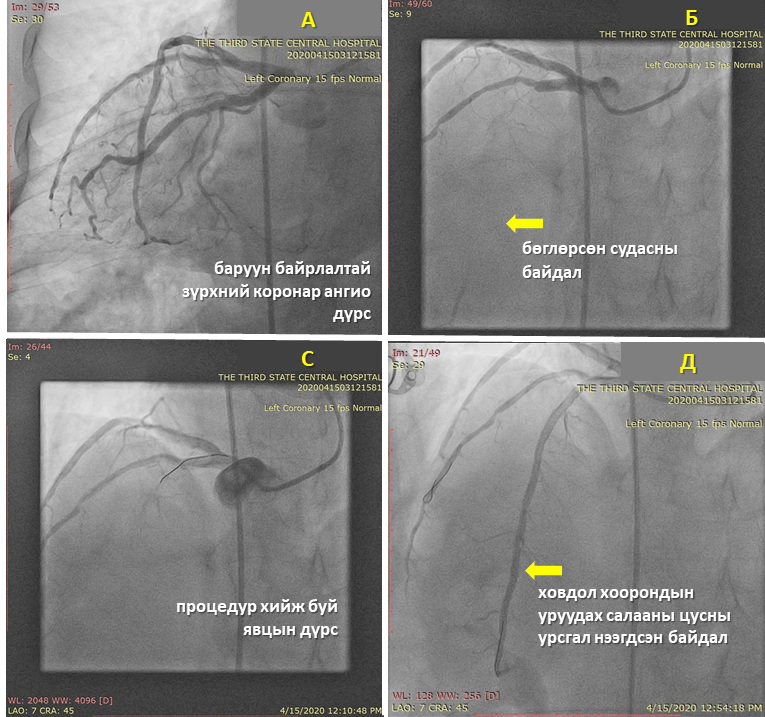

2020 оны 04 сарын 15-ны өдөр тус эмнэлгийн Ангиографийн оношилгоо, эмчилгээний тасгийн зөвлөх эмч АУ-ны доктор, профессор З.Лхагвасүрэн ахлагчтай судсан дотуурх мэс засал эмчилгээний баг төрөлхийн баруун байрлалтай зүрхтэй 57 настай эмэгтэйд титэм судсан дотуурх мэс заслын аргаар баруун цавины артериар дамжиж баруун байрлалтай зүүн титмийн артерийг сэтгүүрдэж, архаг бөглөрөлт бүхий ховдол хоорондын уруудах салааны судсанд 2 ширхэг эмтэй тэлэгч стентийг суулгаж, титмийн цусны урсгалыг нээж, зүрхний булчингийн цусан хангамжийг сэргээх эмчилгээг амжилттай хийж амь насыг нь аварлаа.

Баруун байрлалтай зүрхтэй хүний титэм судасны эхлэл хэсгүүд хэвийн бус байрлалтай байдаг онцлогоос шалтгаалан титэм судсан дотуурх мэс заслын аргаар оношилгоо, эмчилгээ хийхэд стандарт арга барилаас өөр байдаг тул зарим тохиолдолд өвөрмөц, тусгай зориулалтын хэрэгсэл ашиглах шаардлага гарч, ажилбар хийж буй эмчээс илүү туршлага, ур чадвар шаарддаг юм.

Мэс ажилбарын үед ямар нэгэн хүндрэл гараагүй бөгөөд эмчлүүлэгчийн биеийн байдал, эмчилгээний үр дүн сайн байна.